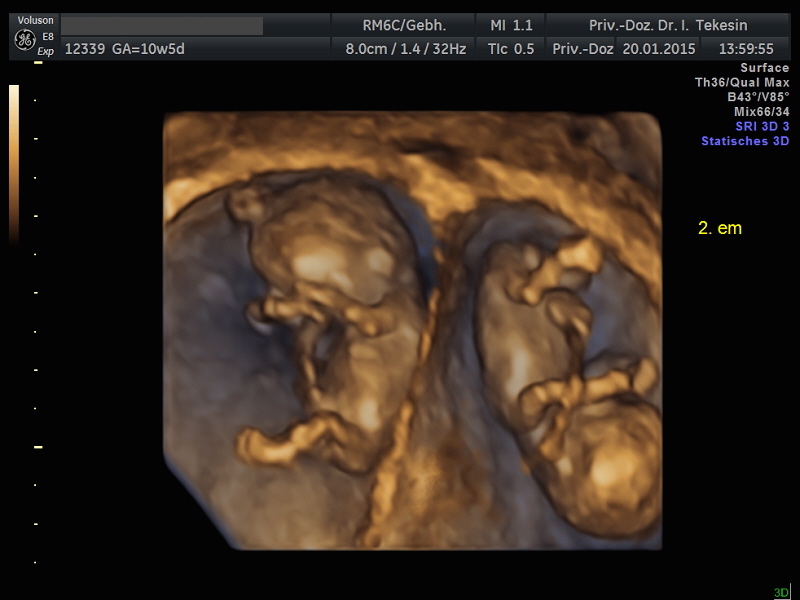

3D-/4D-Ultraschall (optional)

Immer mehr werdende Eltern interessieren sich für die faszinierenden Bilder, die dieses Verfahren liefert. Die plastische, dreidimensionale Darstellung der Oberfläche des Gesichts und anderer Körperregionen wird durch spezielle Bildrekonstruktion in schnellen Rechnern erreicht. Auch einzelne innere Organe oder „Gefäßbäume“ können von allen Seiten betrachtet werden. Viele dünne Schnittebenen (2D) werden zu einer gemeinsamen 3D-Sichtweise im Computer des Ultraschallgerätes zusammengeführt. Unter einem 4D-Ultraschall versteht man darüber hinaus eine 3D-Ultraschalluntersuchung unter Echtzeitbedingungen. Anstatt nur statische Bilder anzuzeigen, erfasst ein 4D-Ultraschall die Bewegungen des Kindes, weshalb er auch als „Live-3D-Ultraschall“ bezeichnet wird.

Diese Vorgehensweise ermöglicht äußerst realistische Bilder, bei denen sogar Gestik und Mimik des Kindes in bewegten Sequenzen festgehalten werden können. Die Untersuchung kann wie auch der normale Ultraschall während des gesamten Schwangerschaftszeitraums durchgeführt werden. Möchte man das Ungeborene komplett sehen, wird die 12. bis 16. Schwangerschaftswoche empfohlen, die Zeit zwischen der 28. und 33. Schwangerschaftswoche eignet sich besonders zur präzisen Darstellung einzelner Körperteile

Wir sehen in diesem modernen Verfahren in erster Linie eine ergänzende Maßnahme bei speziellen Fragestellungen bezüglich Herz, Gehirn oder Skelett und vor allem bei Verdacht auf eine fetale Besonderheit.

Dichoriale Zwillinge in der 11. Woche (3D-Darstellung)

Monochoriale Zwillinge in der 13. Woche (3D-Darstellung)